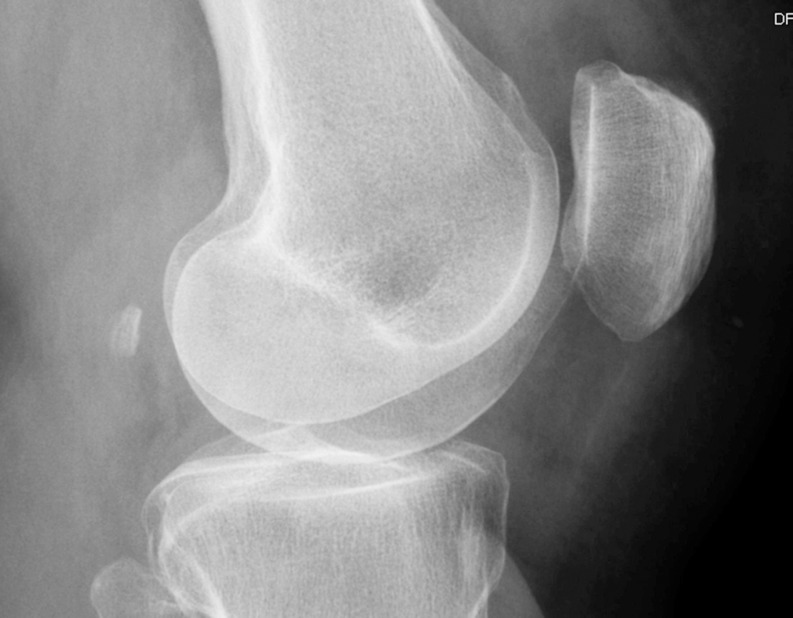

Purpose: The fabella is a sesamoid bone located posterior to the lateral femoral epicondyle within the gastrocnemius muscle. While commonly present in mammals, its prevalence in humans remains unclear, with reported rates ranging from 3 to 87%. Fabella is more frequently observed in Asian and Australian populations but is rare in European and American populations. Although often asymptomatic, it can sometimes cause knee pain, known as "fabella syndrome," and may contribute to neurological symptoms when in proximity to the common fibular nerve. Given the limited awareness of fabella's presence, this study aims to assess its prevalence and anatomical characteristics to aid in the differential diagnosis of knee pain.

Methods: A retrospective analysis was conducted on 500 knee radiographs from 383 patients experiencing knee pain. Data collected included patient age and sex, fabella presence and dimensions, fabella location (distances to surrounding bony structures), patella dimensions, and patellotibial ligament length.

Results: Fabella was detected in 31 females (14.76%) and 29 males (25.66%). Among the examined knees, fabella was present in 40 (12.82%) of female and 39 (20.74%) of male knees. The mean fabella length was 8.85 mm (SD = 2.59), and thickness was 5.63 mm (SD = 1.88), with no significant sex differences. No correlation was found between fabella size and patella dimensions. Notably, patients with fabella were older on average, and bilateral fabellae were significantly larger than unilateral cases (p < 0.05).

Conclusion: Fabella is a relatively common anatomical variant in Central European populations, present in one in six women and one in four men. Its increased prevalence in older individuals suggests a potential age-related development. A comprehensive understanding of fabella anatomy may aid clinicians in diagnosing and managing unexplained knee pain, particularly in elderly patients.